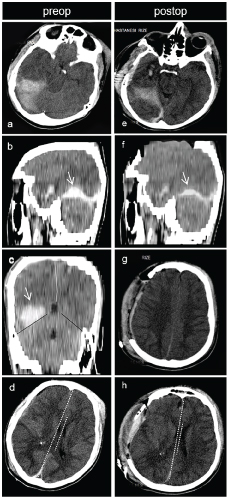

No sign of a significant haemorrhage. Sections bring to mind that diffuse axonal injury with petechial contusions. View Figure 1

Figure 2: (preoperative images): a) 6 hours later from admission to intensive care of the patient’s CT images; b,c) Peritentorial bleeding is observed on axial CT section. Blood volume on sagittal and coronal sections of CT is better understood; d) Midline shift from right to left and minimal subdural hemorrhage on right cerebral hemisphere surface. Postoperative images: Postoperative CT images in 12 Hours; e,f) Compared to the previous section in Figures 2a and Figure 2b are followed by the decreases of the peri-tentorial blood volume and midline shift decreased observed. View Figure 2

The clinical situation was considered to be cerebral herniation due to anisocoria, hyperventilation despite the suppression of the sleep-inducing drug, and bradycardia from time to time, diffuse brain edema in the brain CT and the midline shift. However, the localization of bleeding was a very rare one; therefore, the proper approach was decided to primarily stop the herniation. Due to the difficulty in direct access to the hematoma and the increased pressure in the right cerebral hemisphere, decompressive craniectomy was performed on the right hemisphere in an emergency fashion in order to de-stress the temporal base. Duroplasty was performed via fascia lata and the cranial piece was left inside the leg where the fascia lata had been obtained. The herniation was stopped after the operation. His respiration pattern improved and anisocoria regressed. Neurological wellness was confirmed by the control brain CT images. The cisternae that had been observed to have been obliterated around the brain stem re-appeared and the midline shift regressed to 2-3 mm (Figure 2e, Figure 2f and Figure 2g). A very surprising outcome was also observed. Although the hematoma was not accessed directly, the volume of peritentorial hematoma was observed to have decreased (Figure 2h).